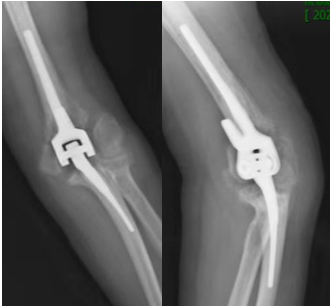

手术如期而至,赵阿姨既忐忑又期待,心中有着远离家人求医的紧张不安、对手术的恐惧,还有对新生活的无限期待。护理团队在术前对赵阿姨给予了更多的关注,理解她的焦虑情绪,进行着心理的安抚和护理,详细的术前术后康复知识的宣教,让阿姨了解了手术的康复过程,在很大程度上缓解了阿姨的不安。在与手术室、麻醉科等紧密配合下,赵阿姨在全麻下行“左侧肘关节置换术”。手术十分顺利地完成了,生命体征及各项指标都正常,整个围术期也进行了科学镇痛处理。术后影像资料显示:人工肘关节假体位置满意。

术后复查X线报告